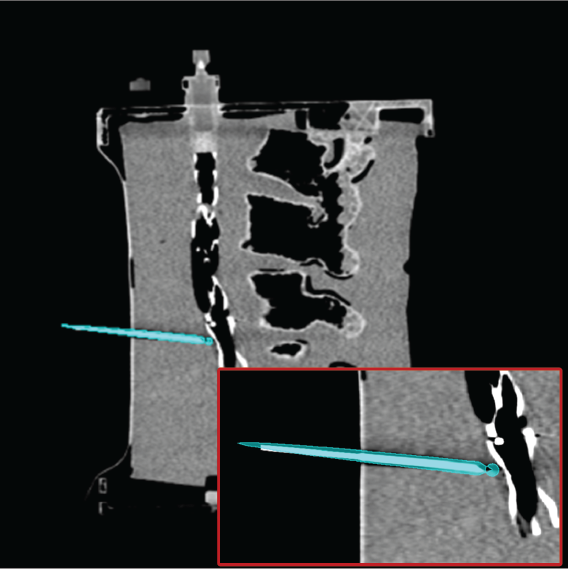

3.4 Phantom experiments

A phantom targeting experiment was conducted to evaluate the accuracy of needle insertion. Fig. 9A shows the experimental setup, including an endoleak phantom, an FG mounting frame, and a Canon Alphenix C-arm (Canon Inc., Tokyo, Japan). Three magnetically tracked needles were inserted into the endoleak phantom. During 2D navigation, the tracked needles (red lines) were projected on the fluoroscopic image, while the actual needles appeared as dark lines. The discrepancies between the two were used to quantify 2D targeting accuracy.

Fig. 9B illustrates the 3D navigation, including 3D reformations, the rendered contrast-enhanced CT volume, and tracked needles. To validate 3D needle insertion accuracy, we acquired a post-insertion non-contrast CT image (Fig. 9C). The inserted needles were clearly visible in three orthogonal views, with the 3D view displaying the inserted needles in silver and the tracked needles in cyan. Needle tip and angle errors were calculated by comparing the tracked needles with their segmented counterparts from the CT image. This process was repeated three times, with a total of nine inserted needles. The overall needle insertion errors were for the tip, and for orientation, as shown in Table 5.